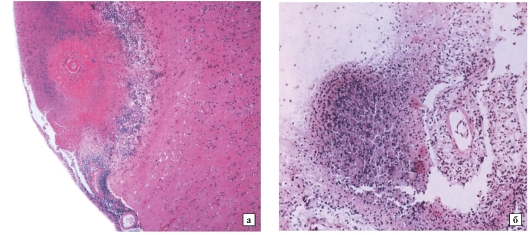

Микроскопический взгляд на мишитарный туберкулез легкого: фотодокументация

Раздел: Снимки-откровения